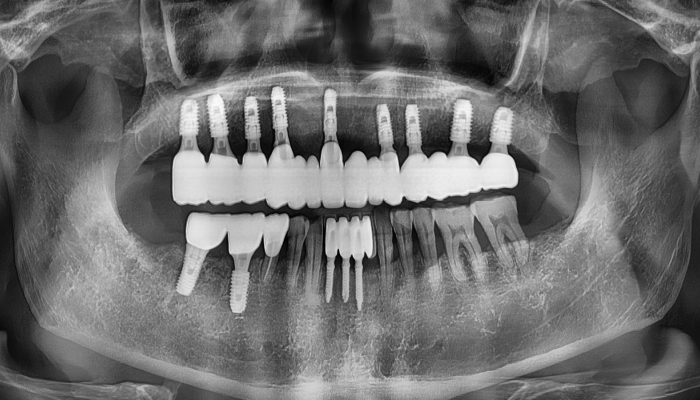

임플란트 | 내비게이션 임플란트 수술

환자명 남OO 치료기간 8주 한줄 설명 식립갯수 : 10개

• 식립갯수 : 10개